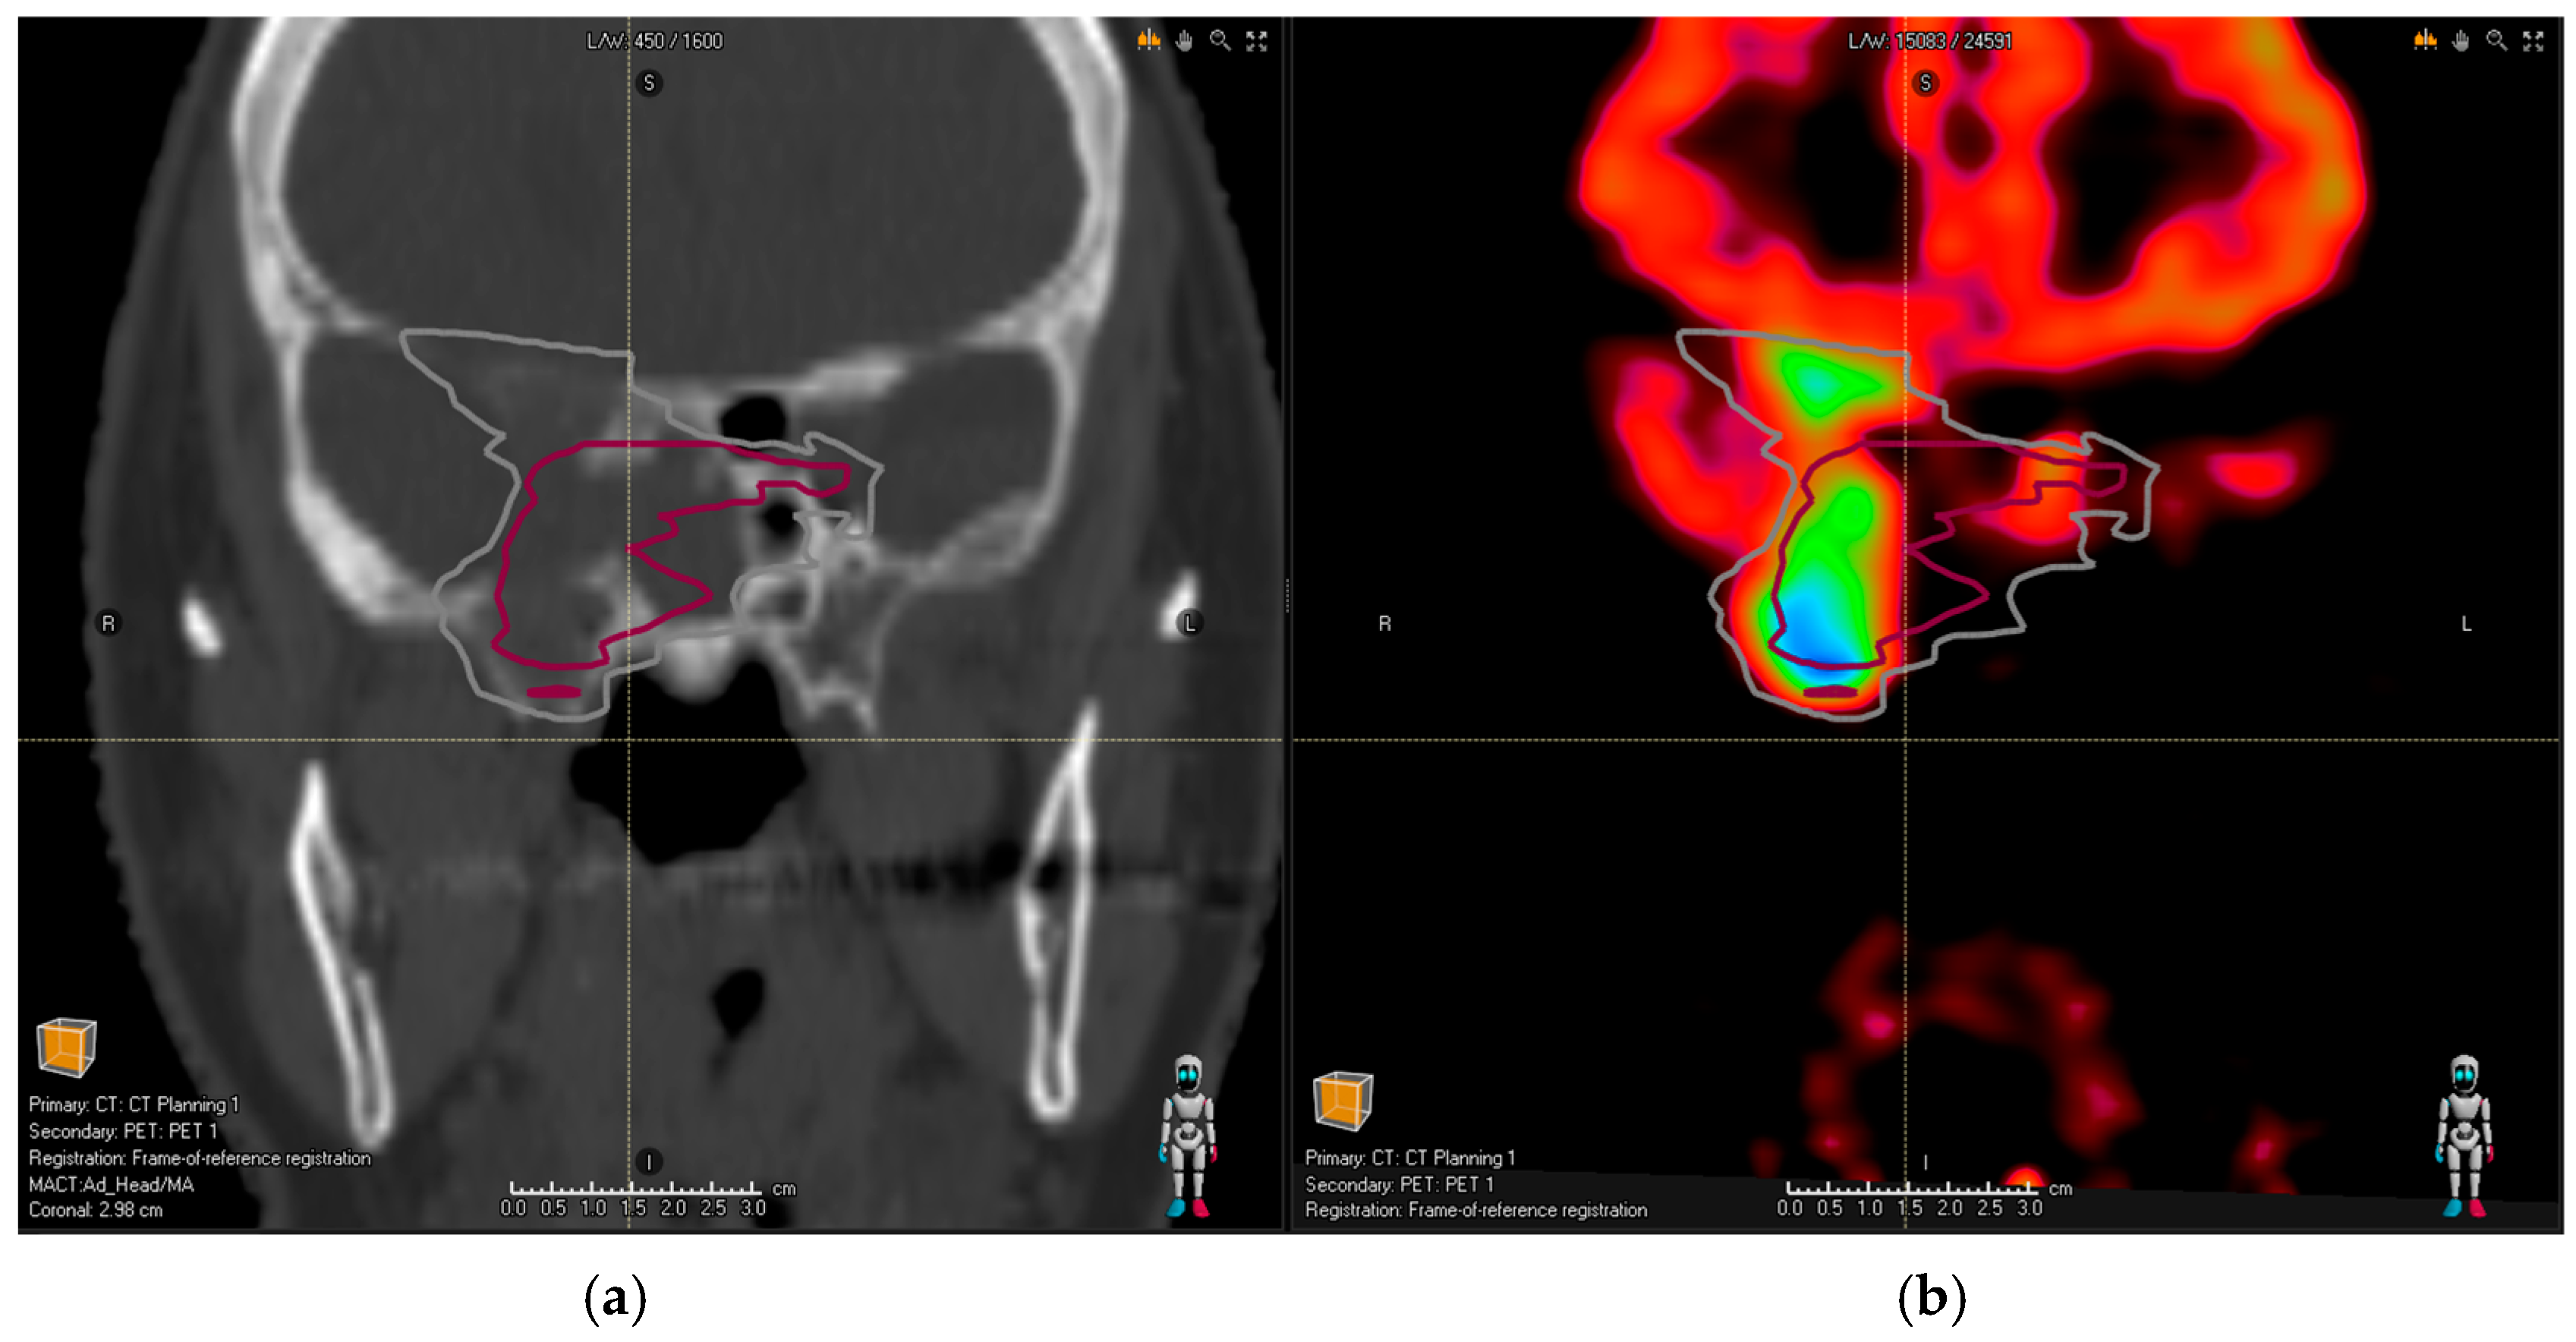

Figure 1. (a) Planning the CT image of a patient with pituitary adenoma. Pink contour shows common MRI volume; after the addition of PET/CT, (b) the observers identified an infiltration in the left cavernous sinus (white contour). - Extensive bone infiltration in the frontobasis area from a case of an aggressive PitNET (as depicted in Figure 2).

Figure 2. Planning CT image (a) of a patient with an aggressive pituitary adenoma. Red contour shows the common MRI volume of all observers; (b) the addition of PET/CT revealed further bone infiltration into frontobasis (difficult to identify based on structural imaging alone as the patient had co-existing osteoporosis)—the gray contour representing common PET/CT and MRI volume takes this finding into account.

In all these cases, the new tumor volume first identified with the aid of DOTA PET/CT should be considered relevant for the proton treatment plan. There was no relevant tumor volume missed by observers in MRI compared to PET/CT for glomus tumors. Figure 1a shows the planning CT image of a patient with pituitary adenoma; Figure 2a shows the planning CT image of a patient with an aggressive pituitary adenoma.